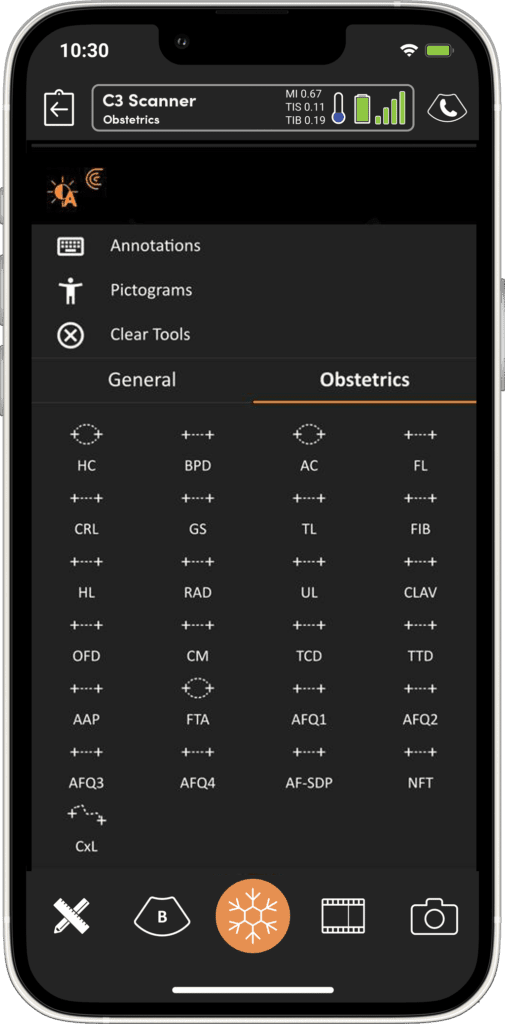

Imagerie Obstétricale Optimisée

I feel more confident with my ultrasound exams since I’ve started using OB AI. I love how the AI makes the app light up when things are perfectly lined up – I can see this really helping both seasoned clinicians and those who are starting their ultrasound journey.